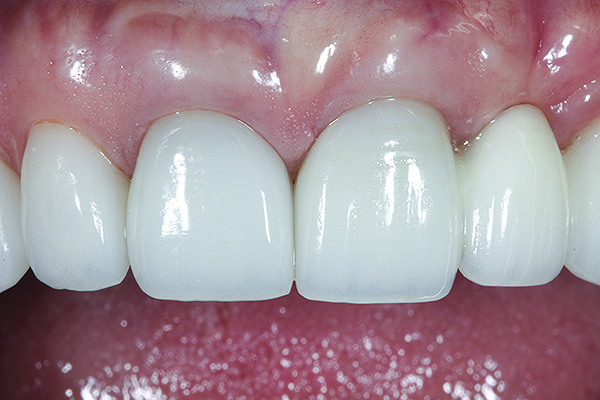

The crown was inserted and secured with a luting composite (Multilink® Automix, Ivoclar Vivadent) (Figure 17); a radiograph confirmed complete removal of excess cement (Figure 18). At the 4-month follow-up appointment, the soft tissues were healed within normal limits, and the patient was pleased with the esthetic outcome of the definitive restoration (Figure 19 and Figure 20).

Fig 19 and Fig 20. Four-month follow-up appointment. The soft tissues had healed within normal limits (Fig 19), and the patient was pleased with the esthetic outcome of the definitive restoration (Fig 20).